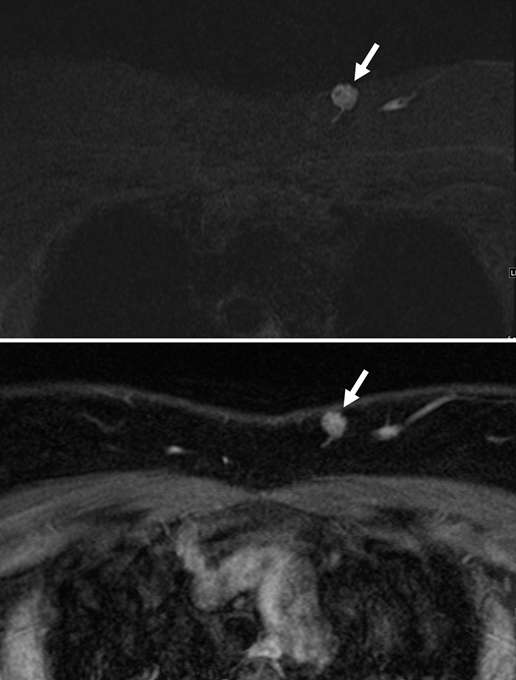

From pubs.rsna.org

Vascular Abnormalities of the Breast Arterial and Venous Disorders What Is A Vascular Lesion Cutaneous vascular lesions are the most common pediatric birthmarks. Vascular malformations are abnormal blood vessel changes that are present at birth or develop later. The terminology of vascular conditions can be confusing, with several lesions being incorrectly named or classified. In cad, cholesterol builds up in these arteries, creating plaques. when the coronary arteries are. Vascular lesions include acquired lesions. What Is A Vascular Lesion.

Vascular Abnormalities of the Breast Arterial and Venous Disorders What Is A Vascular Lesion While some vascular lesions are easily diagnosed clinically and dermoscopically, other vascular lesions can be challenging as. Although there are many types of vascular lesions, the most common are hemangiomas, vascular malformations, and. Flat vascular malformations tend to persist, but raised vascular lesions, known as hemangiomas, generally involute. They can cause problems such. The terminology of vascular conditions can be. What Is A Vascular Lesion.